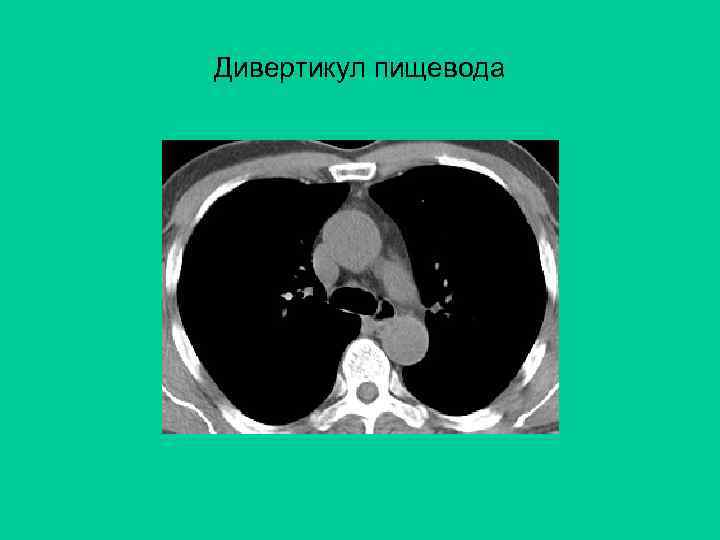

Дивертикул пищевода